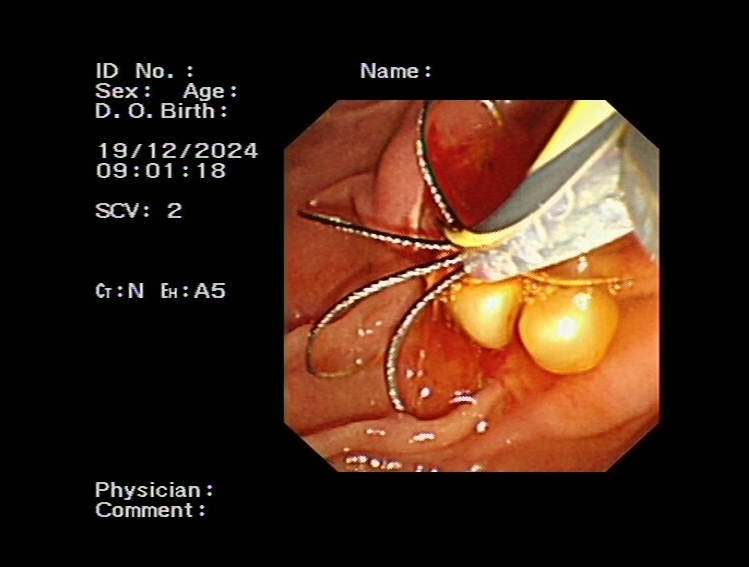

對于無法手術切除的膽管或胰腺惡性腫瘤導致的梗阻性黃疸,可以進行ERCP下膽道支架植入,以緩解梗阻性黃疸癥狀,提高患者生活質量。通過光動力、射頻消融等治療,還可以控制腫瘤的生長,提高膽道支架的通暢期,延長患者生存時間。

膽道惡性梗阻膽道支架置入

膽道腫瘤光動力治療